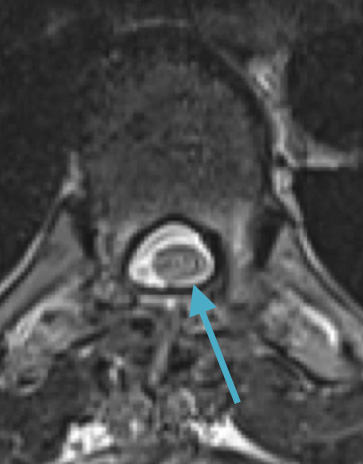

Postoperative MRI T1w demonstrating interval resection with cord re-expansion (blue arrow)

Postoperative MRI T1w demonstrating a gross total resection